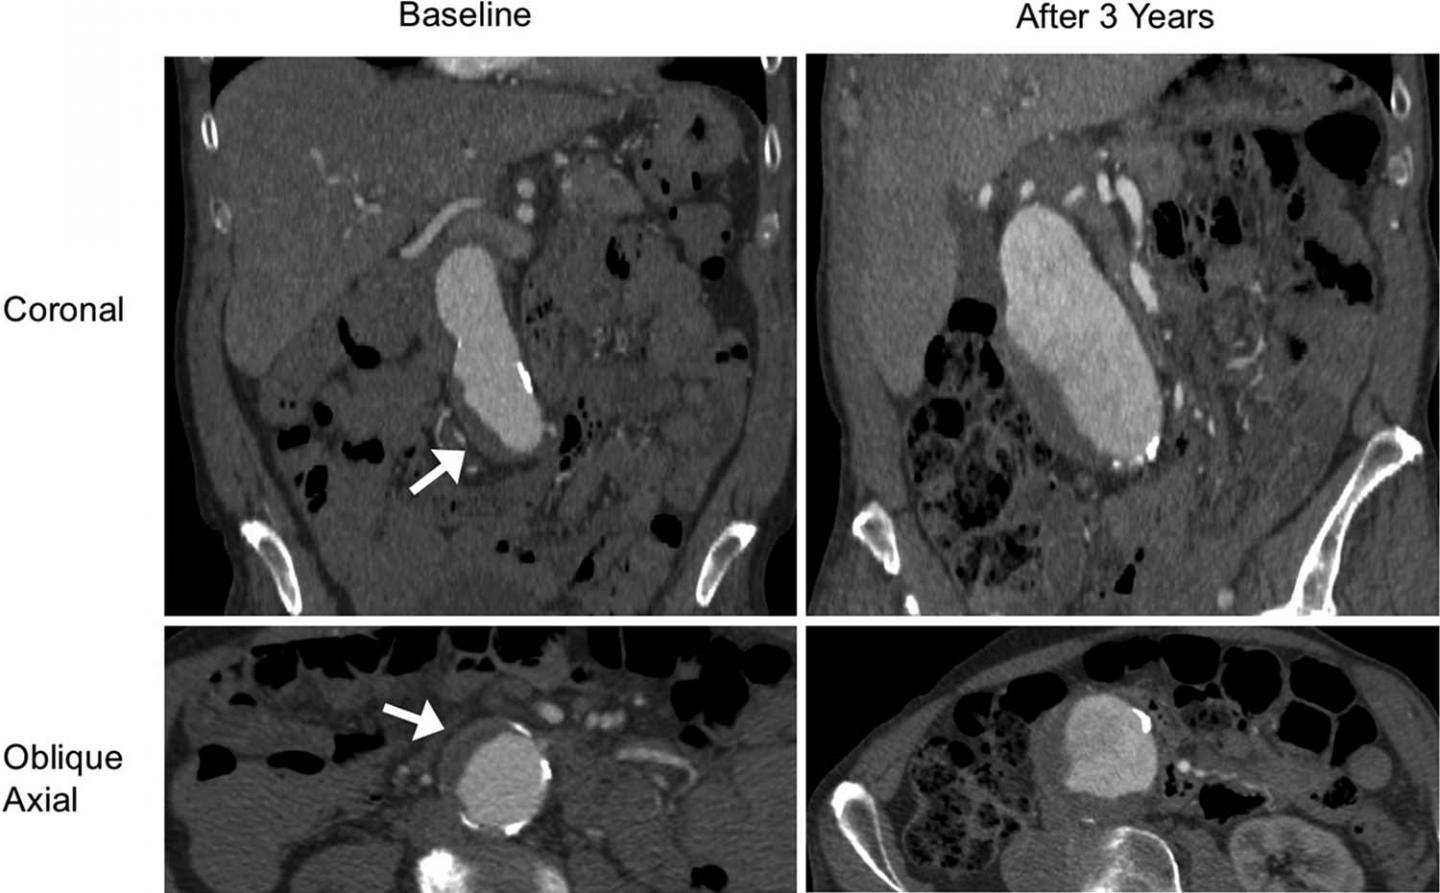

image: A patient (aged 85 years, male) with a fast-growing abdominal aortic aneurysm with intraluminal thrombus at baseline. Contrast-enhanced CT images (coronal and oblique axial planes) show that the aneurysm grew from 4.1 to 6.3 cm within 3 years at a growth rate of 7.3 mm/y. Arrow shows the intraluminal thrombus.

Slightly more than half of patients had an intraluminal thrombus. The aneurysms of those with intraluminal thrombus were larger at baseline and grew by a rate of 2 millimeters (mm) per year, twice as fast as the 1 mm per year growth rate in people without intraluminal thrombus.